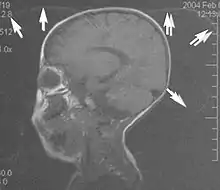

A motion artifact is one of the most common artifacts in MR imaging.[2] Motion can cause either ghost images or diffuse image noise in the phase-encoding direction. The reason for mainly affecting data sampling in the phase-encoding direction is the significant difference in the time of acquisition in the frequency- and phase-encoding directions.[1] Frequency-encoding sampling in all the rows of the matrix (128, 256 or 512) takes place during a single echo (milliseconds). Phase-encoded sampling takes several seconds, or even minutes, owing to the collection of all the k-space lines to enable Fourier analysis. Major physiological movements are of millisecond to seconds duration and thus too slow to affect frequency-encoded sampling, but they have a pronounced effect in the phase-encoding direction. Periodic movements such as cardiac movement and blood vessel or CSF pulsation cause ghost images, while non-periodic movement causes diffuse image noise (Fig. 1). Ghost image intensity increases with amplitude of movement and the signal intensity from the moving tissue. Several methods can be used to reduce motion artifacts, including patient immobilisation, cardiac and respiratory gating, signal suppression of the tissue causing the artifact, choosing the shorter dimension of the matrix as the phase-encoding direction, view-ordering or phase-reordering methods and swapping phase and frequency-encoding directions to move the artifact out of the field of interest.[1]